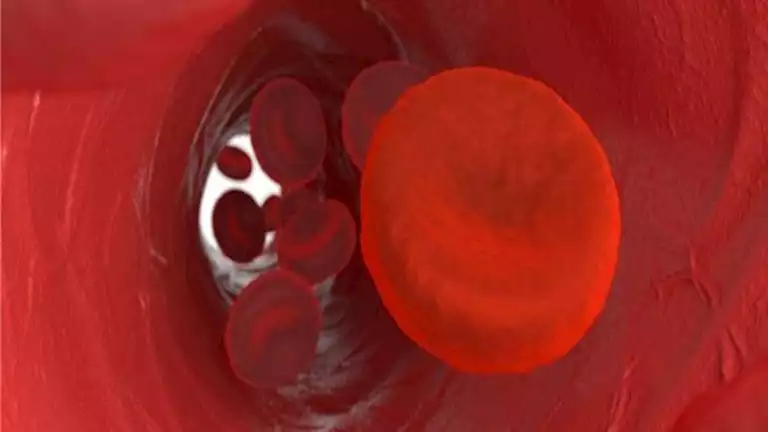

مع ارتفاع درجات الحرارة في فصل الصيف، يعاني كثيرون من الخمول وتراجع مستويات الطاقة.

ونصحت الدكتورة نهلة عبدالوهاب، استشاري التغذية، بتناول مشروبات طبيعية تساعد على تنشيط الدورة الدموية وتحسين تدفق الدم، ما يساهم في تعزيز الشعور بالنشاط والتقليل من الإرهاق.

وأضافت عبدالوهاب في تصريح خاص لـ “مصراوي” أن أبرز هذه المشروبات تشمل عصير البنجر الذي يعرف بغناه بالنترات التي توسع الأوعية الدموية، ما يحسن تدفق الدم ويعزز من الدورة الدموية.